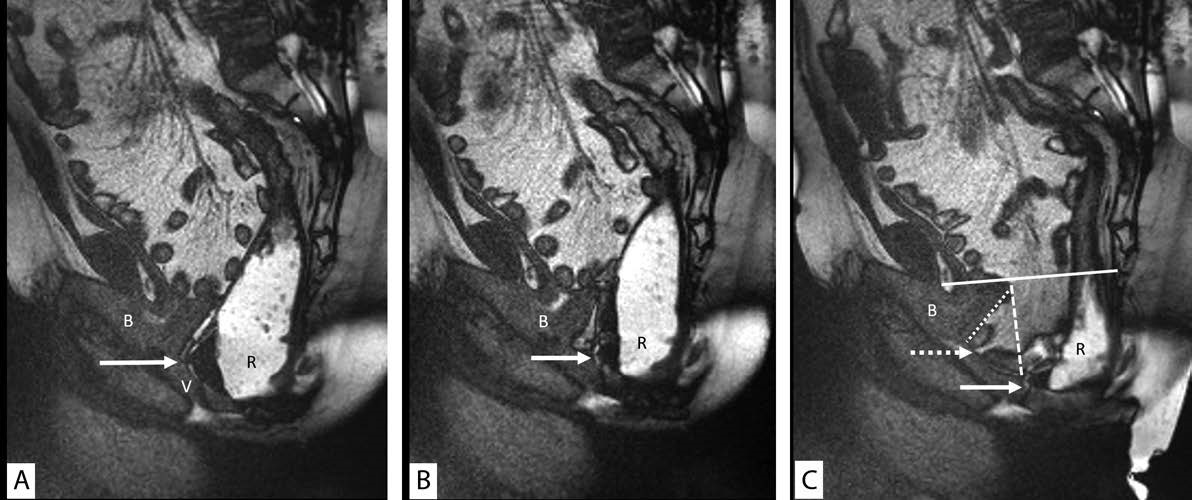

Posterior vaginal wall prolapse is often secondary to rectocele, which is defined as anterior bulging or ballooning of the rectum into the rectovaginal septum. Clinically, rectoceles may cause weakening and lengthening of the vaginal wall and manifest as a posterior vaginal bulge and/ or defecatory dysfunction. However, both rectoceles and cul-de-sac hernias can result in vaginal bulge on physical examination.[28] Furthermore, sometimes rectoceles apparent on clinical examination may not manifest on imaging with MRD. Experts discussed the relatively poor correlation between physical examination and imaging for the detection of rectocele. Decisions regarding appropriateness of surgical repair of rectoceles apparent on imaging and not on physical examination (or vice versa) are often multifactorial based on the patient- and clinicianrelated factors,[30],[31] and discussion of appropriate indications is outside the scope of these guidelines. Nonetheless, the consortium experts agreed that rectoceles should be described when seen on MRD and should be measured in maximal anterior-posterior dimension during defecation. A vertical drawn up from the anorectal junction during defecation extrapolates the normal location of the rectal wall at rest. A horizontal line drawn from this vertical line to the most maximally displaced portion of the anterior rectal wall should be considered the anterior-posterior dimension of the rectocele (Fig. 2C; see Video 2 http:// links.lww.com/DCR/B652) . Furthermore, any resultant deformity of the vaginal wall should be described. Similar to other findings, radiologists should avoid using language that implies severity or grading terminology such as mild/ moderate/severe because the imaging finding may not always correlate with patient symptomatology. Further comment should be made on whether the rectoceles empty with maximum effort or whether they retain contrast. It was noted that contrast retention within a rectocele on MRD does not always correlate with the finding of contrast retention on fluoroscopic defecography, presumably because of differences in consistency between the types of rectal contrast used for fluoroscopy and MRI. When a rectocele does not fully empty, a further comment should be made as to whether the patient can empty fully with digital splinting or manipulation. Furthermore, in patients who have a paradoxical occlusion of the anus or contraction of the puborectalis with defecation, a comment about the timing of the rectocele development in relationship to the timing of the paradoxical contraction of the pelvic floor can provide further insight into the best treatment approach to these patients.